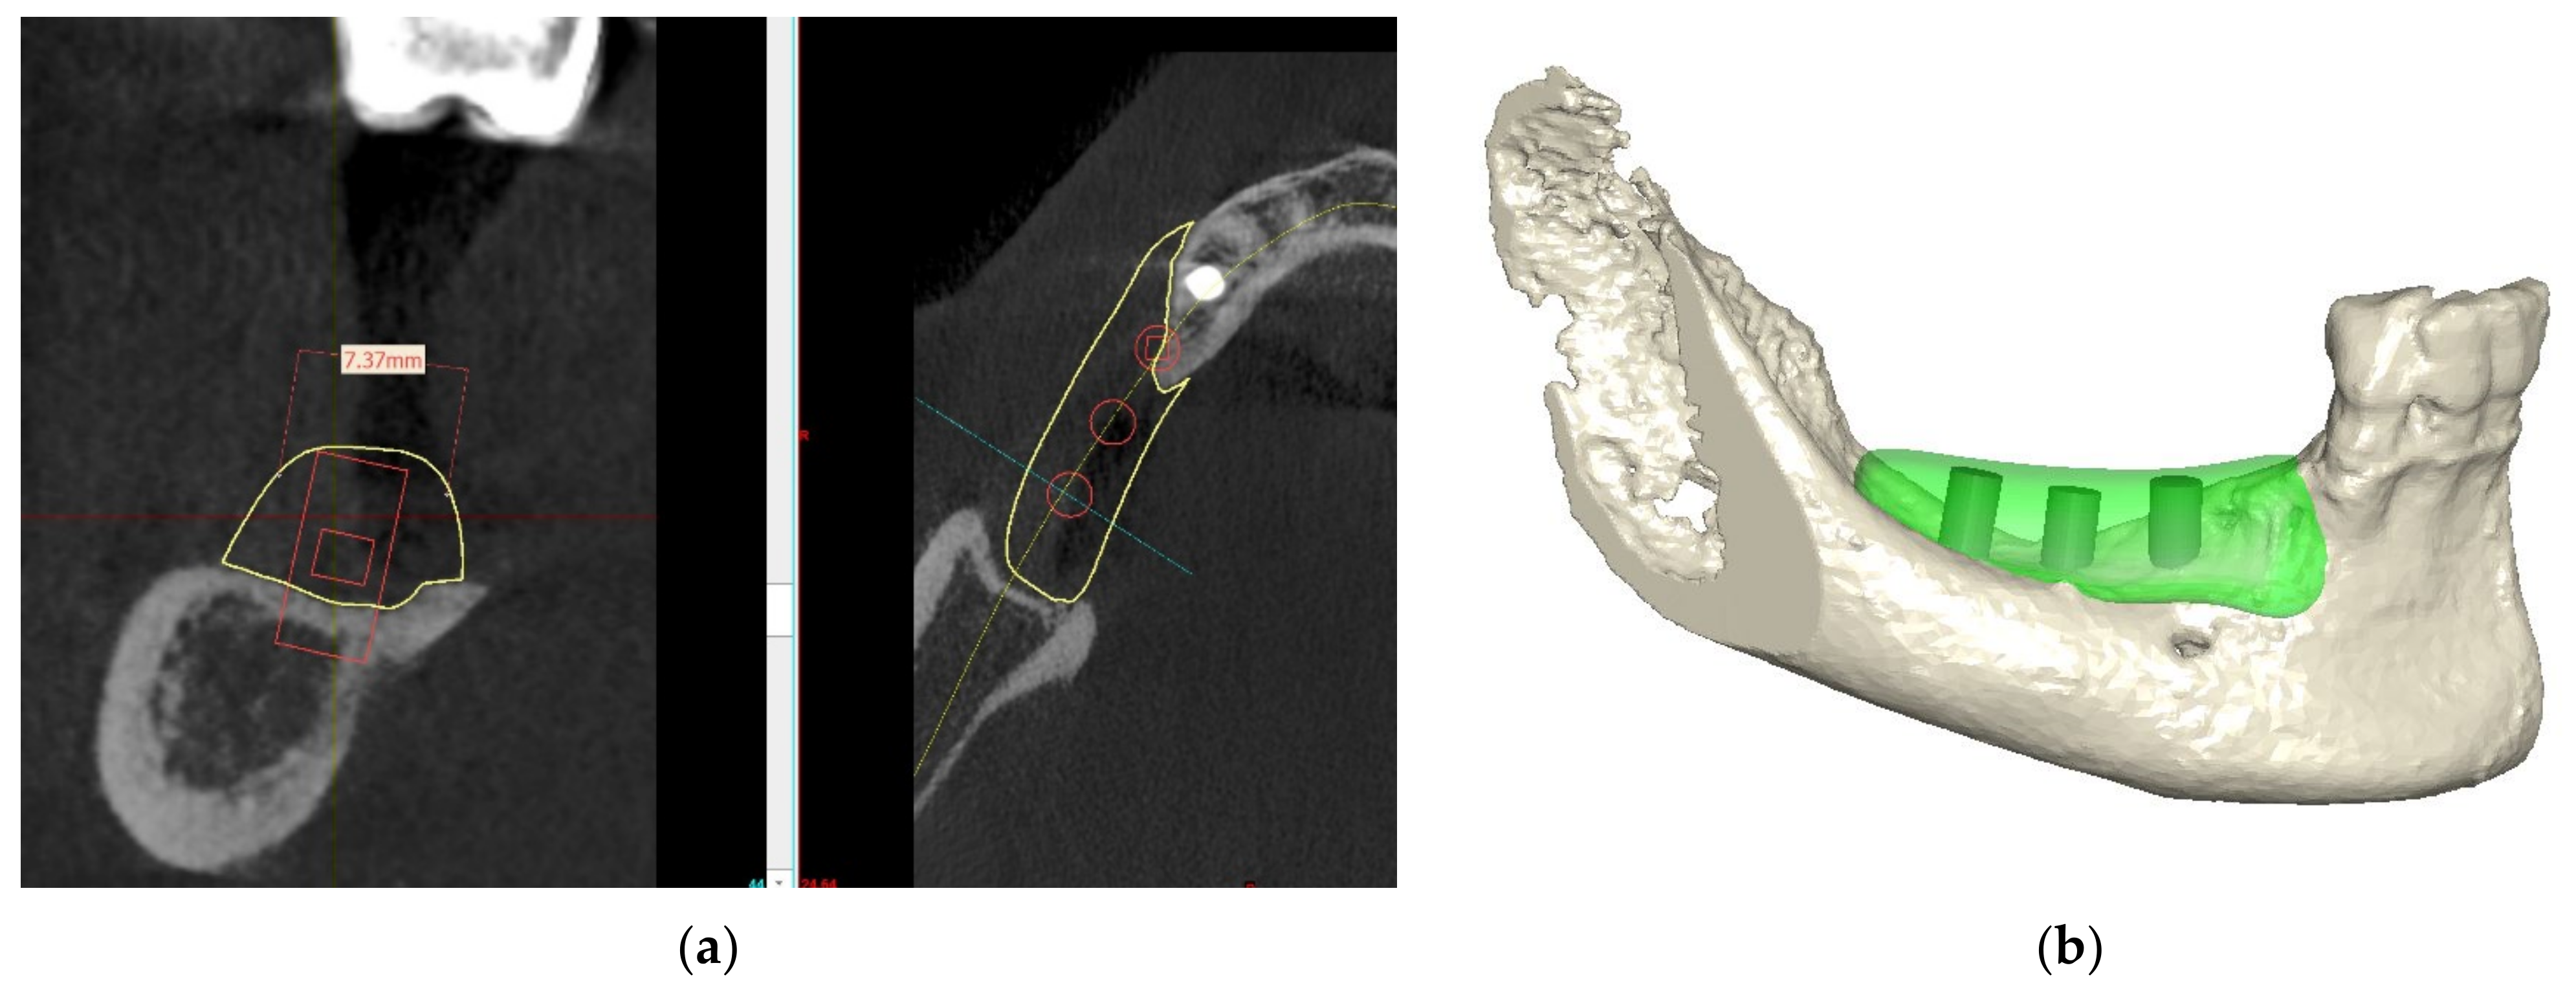

The previous failed implant was left submerged to avoid the potential risks of nerve damage or need of additional grafting. Three implants were planned with a diameter of 3.25–5.0 mm and a length of 10 mm (Figure 13a–c).

Figure 13.

(a–c) Implant planning.

7. Implant Placement

After 6 months of healing, a full-thickness flap was performed, and the screws to retain the ACBB were removed (Figure 14a,b). Three implants were placed with platform switching (Biomet 3i, T3 implants), according to the implant planning, using a surgical (prosthetic) guide. The implants were placed 1mm subcrestally, and a Puros Dermis® Allograft soft tissue matrix (Zimmer Biomet Dental) was placed over the implants to improve the thin tissue phenotype (Figure 15a,b and Figure 16).

Figure 14.

Clinical view before implant placement (a) and a full-thickness flap showing fixation (b).

Figure 15.

Drill guide (a) and implants in place (b).

Figure 16.

Panoramic radiograph showing the implants in place.